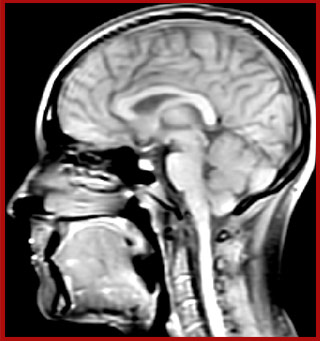

The techniques for measuring myelin have changed a lot over the years. “Since we are using the Elition, our myelin water images are much better. We're now acquiring 1 x 2 x 5 mm voxels and displaying at 1 x 1 x 2.5 mm. For a whole brain we can now measure the fraction of water in the myelin component in only about five or six minutes,” Dr. MacKay says.

of limiting MWI to the brain, even without the cerebellum, we can now spend about the same amount of time and scan the whole brain and the cervical spinal cord, which is a huge boost for us.” Dr. Rauscher says, “For MWI we perform 3D T2 with 32 or more echoes. This used to take a long time, but with Compressed SENSE we can decrease this to ten minutes for the whole head. Because of the large field of view (FOV) on the readout direction, we even get information from the brainstem, which we previously missed when we were using the GRASE approach. Having the whole head scan is nice because it has spatial resolution, orientation and FOV that are comparable to the standard 3D clinical MS scans, including the FLAIR and 3D T2, and a 3D T1 for brain volume.”

T1 - weighted

Myelin water imaging (echo 1)

T1 - Weighted, Myelin Water Fraction Superimposed

Spinal cord coverage

Smaller, more isotropic voxels

Excellent detail in quantitative maps

Images courtesy of Adam Dvorak, Department of Physics and Astronomy, University of British Columbia